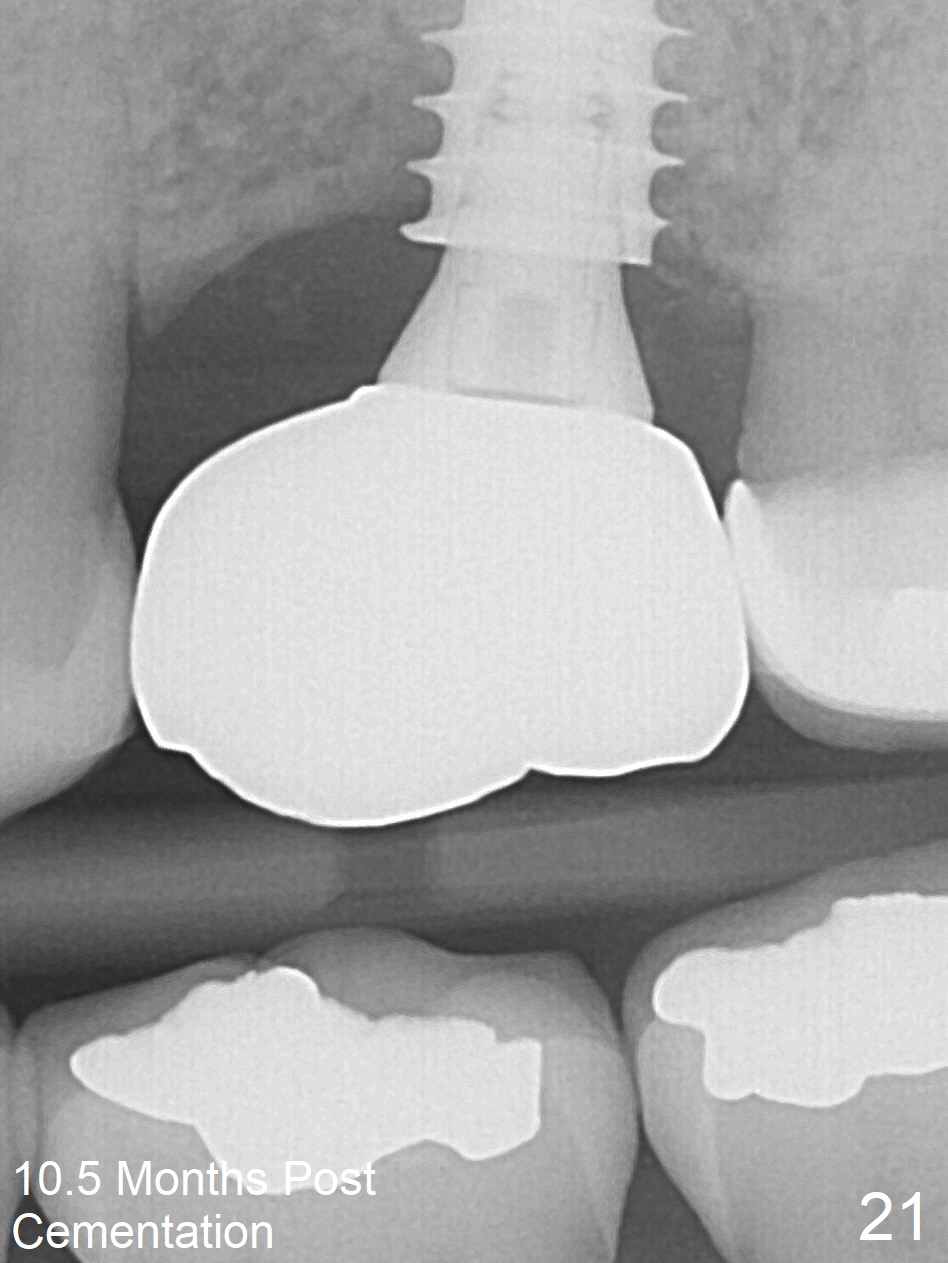

The implant is stable 8 months postop (Fig.15). When a 6x4(3) mm abutment is placed 8.5 months postop, it is distal (Fig.16). The mesiodistal width is 1-2 mm shorter than that at #3, which suggests the mesial shift of the tooth #15. A provisional is fabricated at #14 (Fig.17 P) with supra-occlusion so that there is clearance between the tooth #15 and the opposing one (Fig.18 *). With a separator placed between #14 and 15 (Fig.19), the latter is free to be distalized. Bone volume and density seem to increase 4.5 and 10.5 months post cementation (Fig.20,21, as compared to Fig.15), although the buccal plate remains as concave as shown in Fig.18. One year 5 months post cementation, the patient complains of bad smell from the implant when water pik is being used. It appears that the 1st 2-3 threads are exposed (Fig.22), although the surrounding gingiva remains uninfected. Bone graft is recommended. The site heals without bad smell 7 months post bone graft (2 years 4 months post cementation, Fig.23). The 1st implant thread is found exposed buccal on uncover (regraft?). A small healing abutment is placed because the implant is placed distal (Fig.24). An angled abutment should be tried and #15 crown will be redone. Impression will be taken when the gingiva heals around the provisional crowns.